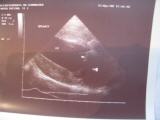

Herzuntersuchung beim Hund

- Herzerkrankungen - Dopplerchokardiographie -